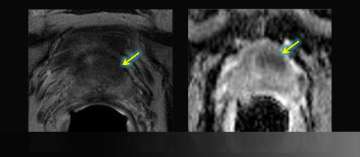

7) MR-Guided Targeted Biopsy

MR-Guided Targeted Biopsy

• 63 y/o, PSA 8.8 → 13.2 over 5 years

• All systematic biopsies negative

• Hypointense left anterior lesion with restricted diffusion is moderately suspicious, not in biopsy zone

• Read More >